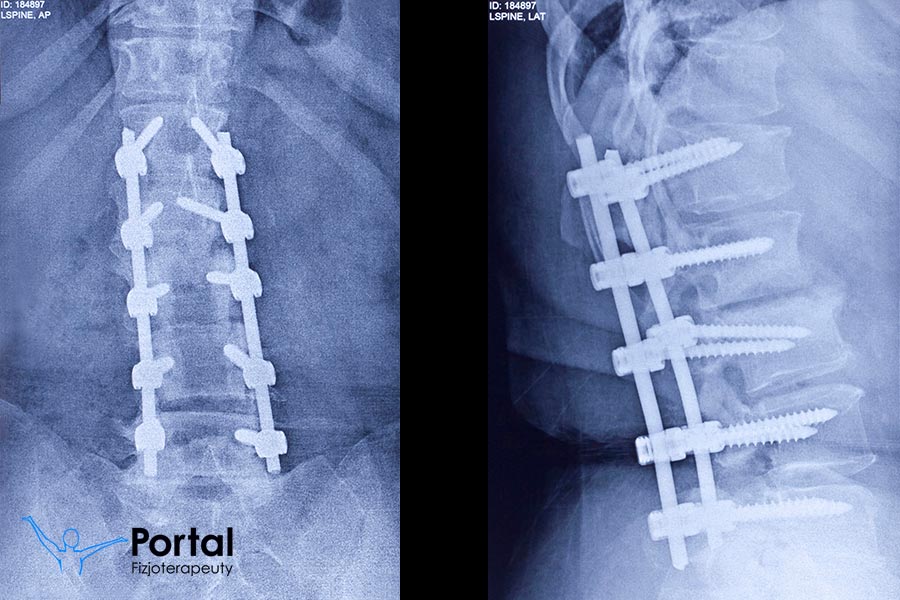

Stabilizacja kręgosłupa

Stabilizacja kręgosłupa to zabieg ortopedyczny, który ma na celu stabilizację odcinka kręgosłupa objętego procesem chorobowym oraz zniesienie ucisku na struktury